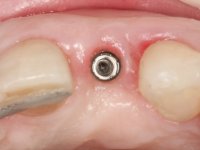

• Colocação de um Implante no local do dente 2.2. Reabilitação do implante com um “abutment” de componente coronário e gengival. em que o orifício de acesso ao parafuso fosse “camuflado” com uma faceta feldspática.

O tratamento iniciou-se com a re -preparação do coto do espigão falso coto fundido, com o objetivo de colocar as linhas de acabamento cervical com uma localização intra-sulcular e simultaneamente confecionar uma coroa provisória adaptada. Com um tratamento ortodôntico muito simples, fechou-se o diastema entre os incisivos centrais superiores e estabilizou-se esta posição com um arame colocado na superfície palatina dos centrais, funcionando como contenção. Posteriormente procurou-se fazer uma tração ortodôntica lenta do dente 2.2 com o intuito de diminuir, ainda que muito ligeiramente a perda óssea vertical nessa zona. Finalizada a tração, foi feita a extração do dente 2.2 e a zona foi reabilitada provisoriamente com uma coroa de resina composta colada aos dentes adjacentes. Foi colocado um implante dentário na zona do dente 2.2 sendo novamente colada a coroa provisória em resina, reabilitando provisoriamente a paciente durante o período de osseointegração. No dente 1.3 foi feita uma gengivectomia com bisturi elétrico, com a intenção de subir o nível cervical do 1.3 conseguindo uma maior harmonia com o dente 2.3. Estabilizados os tecidos moles, foi feita uma impressão com a técnica de moldeira aberta, utilizando silicones de adição de consistência “putty” e “light”. A recolha da cor, tanto da componente dentária como dos tecidos moles foi feita pelo ceramista no consultório.  No laboratório as impressões foram passadas a gesso e deram origem a modelos de trabalho que foram devidamente analisados. Foi decidido confecionar um “abutment” metalo-cerâmico aparafusado sobre o implante. Este “abutment” foi fundido com uma liga nobre e posteriormente revestido a cerâmica coronária e gengival. Dada a inclinação do implante o aparafusamento condicionou de forma inevitável a saída do orifício do parafuso pela superfície vestibular. No sentido de esconder esta situação, o desenho do “abutment” já foi idealizado com a intenção de acomodar na superfície vestibular a colagem de uma faceta feldspática. Este “abutment” foi provado em boca e foram feitos ajustes no componente cerâmico gengival. A sua adaptação aos tecidos moles foi feita tanto de forma subtrativa, com broca, como de forma aditiva, acrescentando resina composta de tonalidade gengival. Este acrescento de resina seria orientador do ceramista na colocação final da cerâmica de tonalidade gengival. A coroa que reabilitaria o dente 1.3 foi cimentada nesta consulta de prova com cimento de ionómero de vidro reforçado com resina composta. Finalizado o trabalho em laboratório da faceta sobre o 1.2 e o “abutment” e a faceta para o implante este foi colado em boca, após a colocação do isolamento absoluto. O trabalho satisfez plenamente a paciente. Durante oito anos a paciente foi seguida regularmente, mostrando-se agradada com o tratamento efetuado, no entanto começou a mostrar interesse em intervir esteticamente nos incisivos centrais superiores. Decidida a segunda fase da nossa intervenção, foi feita a preparação dentária dos dentes 1.1 e 2.1 para a colocação de duas facetas feldspáticas. Particular cuidado foi tido na preparação inter-proximal distal junto ao “abutment” do implante. Foi preciso avaliar muito pormenorizadamente o eixo de inserção da faceta em relação ao “abutment”. As facetas feldspáticas foram confecionadas em laboratório e posteriormente coladas em boca após a colocação de isolamento absoluto. Um ano após, iniciamos a nossa terceira fase de tratamento, após a faceta colada no dente 2.1 ter fraturado. A preparação dentária foi feita sobre a faceta colada, procurando estender mais para palatino o interface inter-proximal distal. O objetivo seria passar para mais palatino do ponto de contacto o interface faceta-dente. O preparo dentário do dente 1.2 também foi muito reduzido, limitando-se a criar um eixo de inserção. Após confecionadas a coroa total e a faceta em laboratório foram coladas em boca. Primeiro foi colada a coroa utilizando-se um isolamento relativo com teflon, posteriormente foi colada a faceta após a colocação do isolamento absoluto. Na coroa utilizei este tipo de isolamento para evitar a utilização de grampos. Seria difícil de aplicar pela forma e dimensão do dente e agressivo para os tecidos moles. Após a colagem foi avaliada a integração oclusal do trabalho.